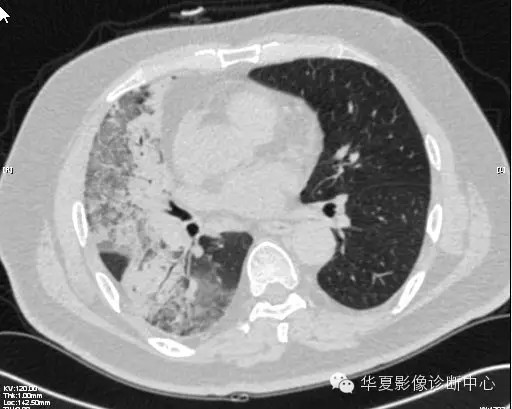

【病例学习】甲型H7N9禽流感一例

男性 63

发热咳嗽5天

2013-4-5拍片示右肺实变,收入院,追问病史,发病期间肌肉酸痛,头痛,无腹痛腹泻,无明显胸闷气急,无意识改变。有高血压病史,无其它病史。

2013-4-7CT进一步检查。

最终诊断:H7N9。